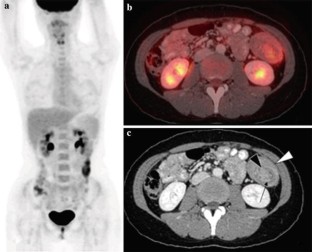

18F-FDG PET/CT in inflammatory pseudotumor of the colon causing intussusception

Inflammatory pseudotumor is a rare benign lesion mimicking malignancy both clinically and radiologically. An accurate diagnosis is still difficult and is based on the histological examination. Since inflammatory pseudotumor is exceptionally rare in the colon, this unexpected lesion can be mistaken for malignancy. We report the first case of inflammatory pseudotumor in the colon that showed 18F-fluorodeoxyglucose (FDG) uptake and acted as the lead point causing colocolic intussusception.

Fig. 2